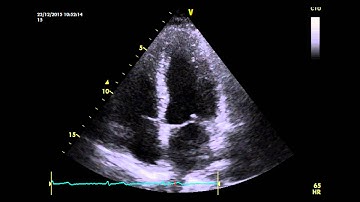

Apical 4 Chamber normal